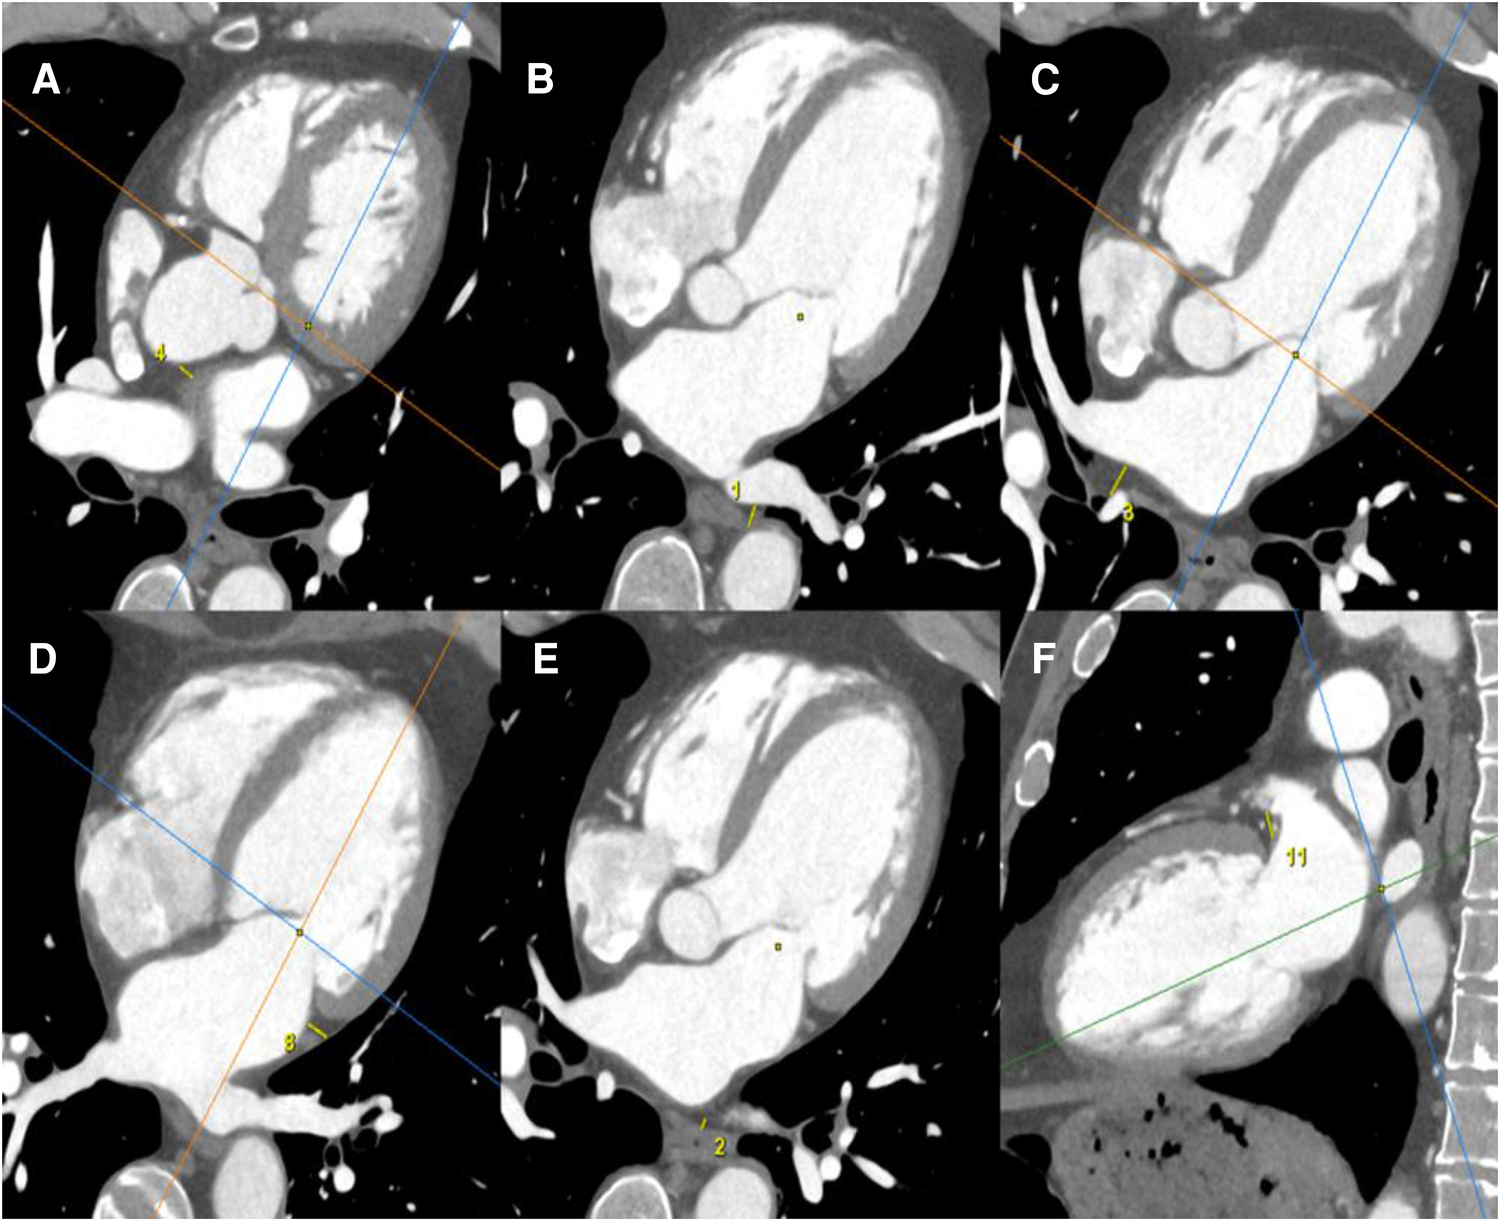

Images were acquired using a 320-row CT scanner (Aquilion ONE Genesis; Canon Medical Systems). Image analysis was performed on a dedicated workstation (AW4.6 workstation; GE Healthcare). All CT scanners were reconstructed in three dedicated cardiac planes, centered on a line (using body imaging planes) from the cardiac apex to the middle of the mitral valve.

EAT was defined as the adipose tissue between the surface of the myocardium and the epicardium. EAT thickness was measured by the same radiologist in millimeters, using a manual 2D caliper, by measuring in the area of maximum thickness the distance between every LA wall and anatomical landmarks, such as the esophagus, for the posterior wall (Figure 2).

Figure 2

EAT measurements were obtained using a cardiac CT scanner. All CT scanners were reconstructed in three dedicated cardiac planes, centered on a line (using body imaging planes) from the cardiac apex to the middle of the mitral valve: short axis plane: perpendicular to true long axis at the level of mid left ventricle; horizontal long axis plane (four-chamber view): horizontal plane perpendicular to short axis; vertical long axis plane (two-chamber view): vertical plane orthogonal to short axis. EAT was defined as the adipose tissue between the surface of the myocardium and the epicardium. EAT thicknesses were measured by the same radiologist in mm, by manual 2D caliper (small yellow line), as the distance between every LA wall and anatomical landmarks: EAT thickness between anterior LA wall and ascending aorta (A); EAT thickness between posterior LA wall and descending thoracic aorta (B); EAT thickness between posterior LA wall and right pulmonary hila (C); EAT thickness between lateral LA wall and visceral pleura of left lung (D); EAT thickness between posterior LA wall and esophagus (E); EAT thickness between periauricular lateral LA wall and mitral root (F).